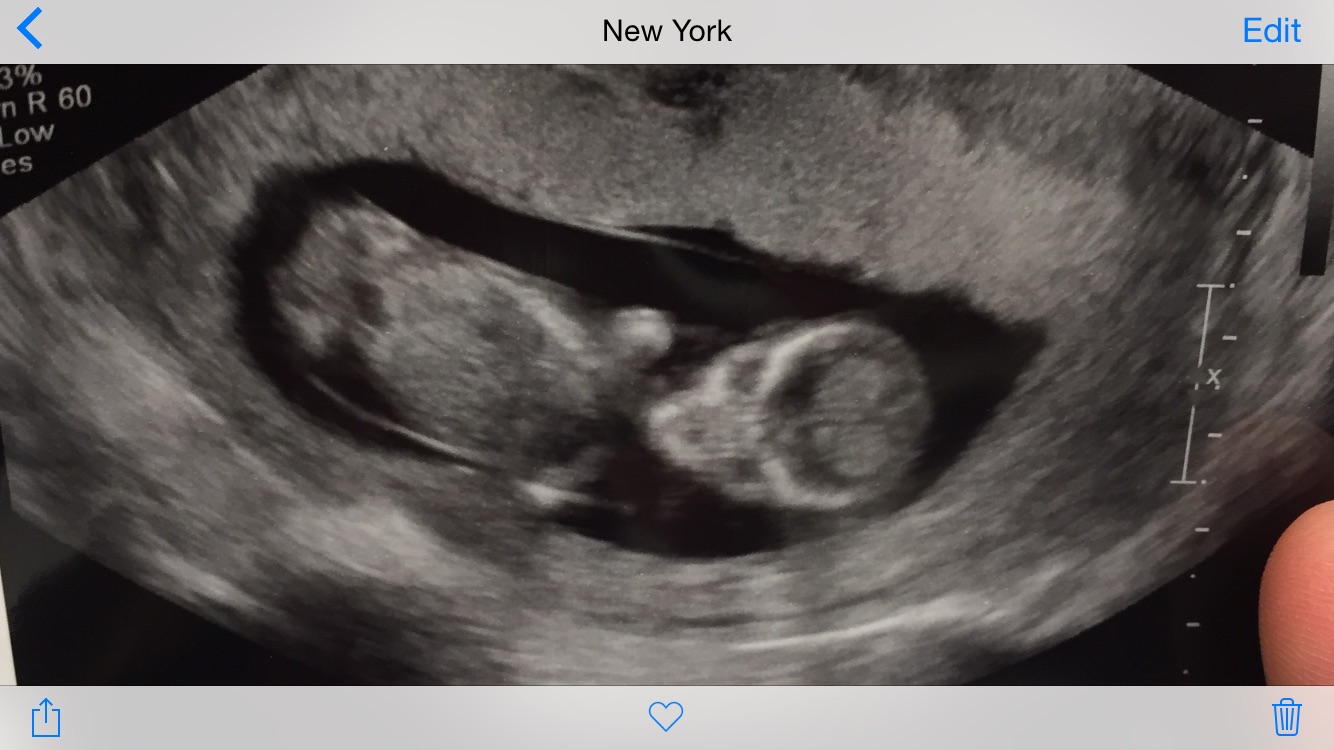

Here are my twins from my 13 week ultrasound. Both have strong heartbeats! One measuring at 13 weeks 4 days and the other 13 weeks 6 days. Tech made a guess and thinks they're boys!!